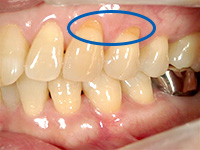

結合組織移植術

右上3番、4番の歯の根が露出していたため、上顎の裏側から結合組織を移植しました。

他の箇所とかわりなく、きれいな歯ぐきになりました。